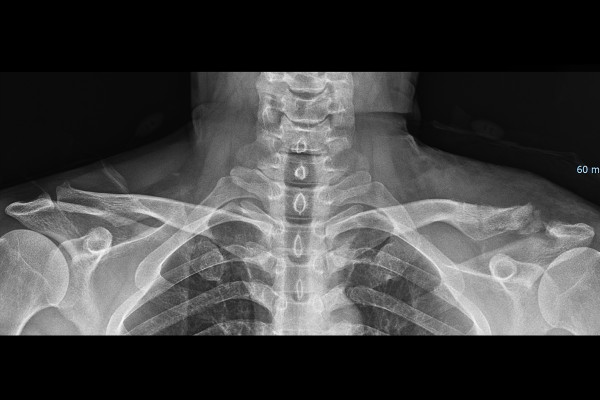

환자분의 어깨 상태를 파악하기 위해서 X-RAY 검사를 시행하였고, 검사 결과, 우측 어깨에는 이상이 확인되지 않지만 좌측 어깨관절은 견봉과 쇄골, 오구돌기와 쇄골이 탈구되어, 높낮이와 거리가 벌어져 있음이 확인됩니다.